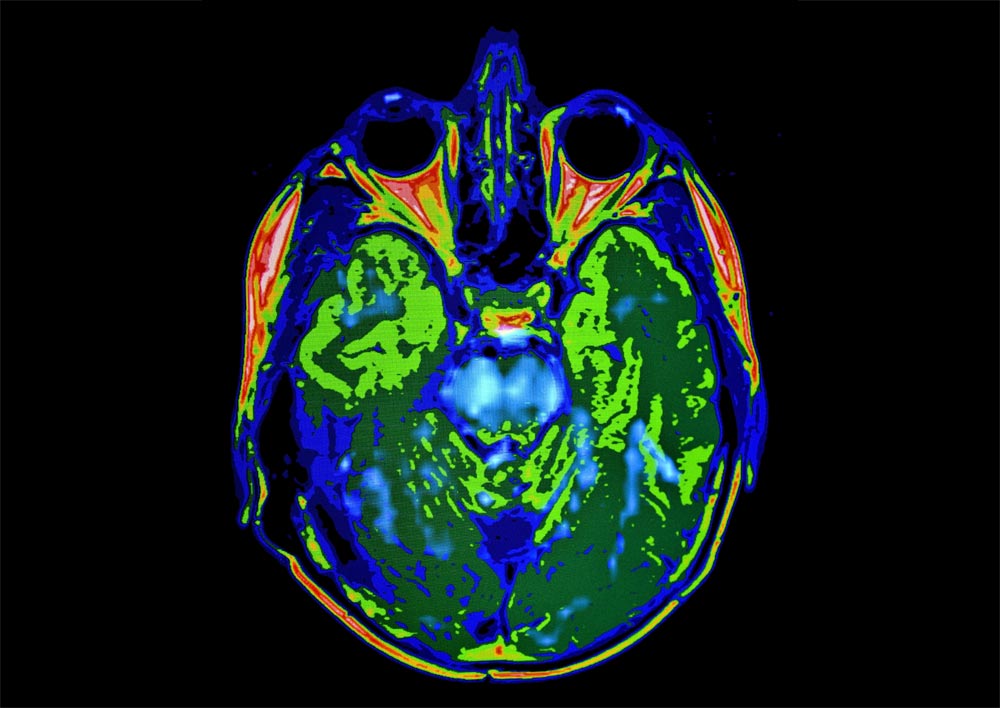

SimonMed Imaging’s new Neuro Degenerative Diagnostic Centers are now offering NeuroQuant quantitative

MRI measurement software as a routine part of SimonMed’s neurodegenerative imaging practice.

NeuroQuant™ is the leading FDA-cleared, fully automated quantitative brain imaging analysis software

which provides high-resolution 3D volumetric analysis of subcortical brain structures and compares them to

a normative database ranging in age from 3-100.

NeuroQuant generates an almost instantaneous color-coded

3D data set of anatomic brain structures along with three graphic volumetric data reports of the patient’s

quantitative brain analysis compared with age-matched controls.

SimonMed’s team of experienced Neuroradiologists are using NeuroQuant routinely on all patients with a

history of memory loss, cognitive impairment, dementia, traumatic brain injury (TBI) and seizures as part of

our standard protocols for these indications. The three automated graphic volumetric reports include a general

morphology report, age-related atrophy report and hippocampal volume asymmetry report. These separate

reports are used together to produce accurate, consistent and reproducible analysis, monitoring and longitudinal

objective tracking of disease progression in patients with Alzheimer’s disease, TBI and seizures increasing

diagnostic accuracy and improving patient care.